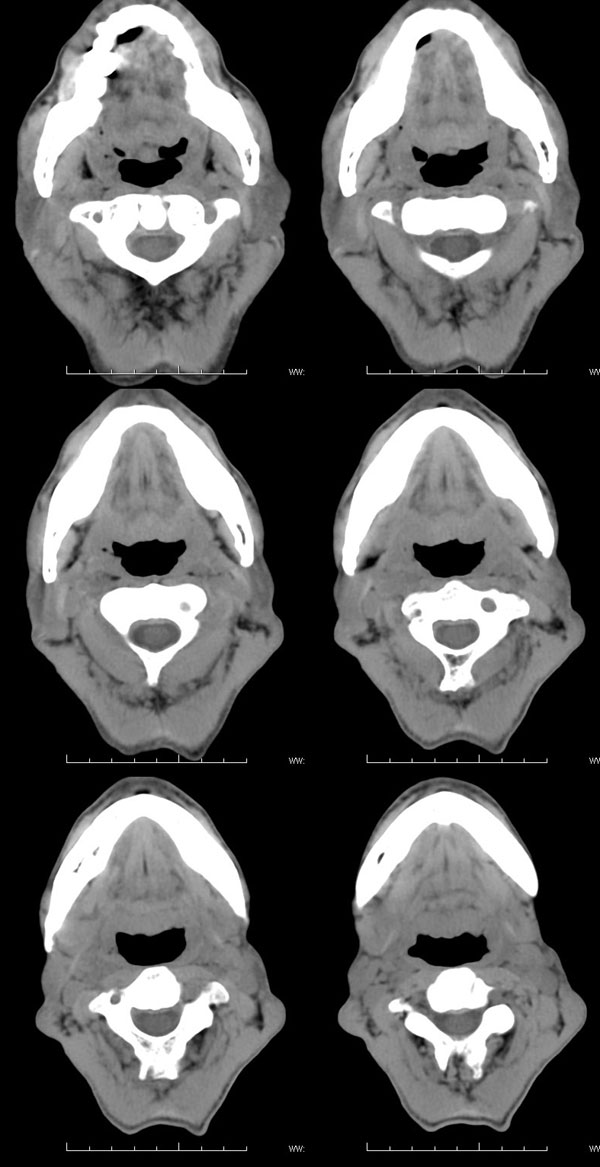

| 男性,57岁。反复声嘶1年,加重半年。 体检:喉粘膜充血,会厌肿胀,上举差,喉室及双声带窥视欠清。              蚂蚁发言:考虑喉癌(声门型)?双侧颈鞘周围淋巴结转移? 徐飞发言:有无呛水?根据病史要考虑球麻痹,脑干应检查 弯三角发言:考虑喉结核,应检查其它部位有无结核 卜一发言:喉腔右侧壁弥漫性软组织增厚,喉腔变窄。支持:喉癌(声门型)!另:双侧颈部多枚淋巴结肿大! 结果: 支纤镜检查:会厌板肿胀,右会厌咽侧壁肿胀,右杓状小结见结节样肿物,喉室肿胀,双声带肿胀、充血,左声带见菜花样肿物,触及易出血,取活检。 病理诊断:高分化鳞状细胞癌。 免疫组化:ck(h)(+++)、pcna(++)、p53(++)、ck(l)(-)。 原贴地址:http://www.radinet.com.cn/forum_view.asp?forum_id=4&view_id=34703 |